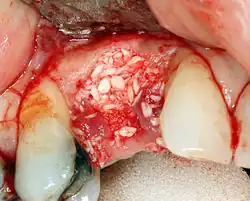

Additional procedures to augment deficient bone in implant site

For an implant to osseointegrate, it needs to be surrounded by a healthy quantity of bone. In order for it to survive long-term, it needs to have a thick healthy soft tissue (gingiva) envelope around it. It is common for either the bone or soft tissue to be so deficient that the surgeon needs to reconstruct it either before or during implant placement.[50]: 1084 All techniques of augmenting the alveolar bone in preparation for implant placement are invasive and associated with a degree of morbidity.[59]

Hard tissue (bone) reconstruction

Bone grafting is necessary when there is a lack of bone. It also helps to stabilize the implant by increasing survival rates of the implant and decreasing marginal bone level loss.[60] While there are always new implant types, such as short implants, and techniques to allow compromise, a general treatment goal is to have a minimum of 10 mm (0.39 in) in bone height, and 6 mm (0.24 in) in width. Alternatively, bone defects are graded from A to D (A=10+ mm of bone, B=7–9 mm, C=4–6 mm and D=0–3 mm) where an implant's likelihood of osseointegrating is related to the grade of bone.[61]: 250

To achieve an adequate width and height of bone, various bone grafting techniques have been developed. The most frequently used is called guided bone graft augmentation where a defect is filled with either natural (harvested or autograft) bone or allograft (donor bone or synthetic bone substitute), covered with a semi-permeable membrane and allowed to heal. During the healing phase, natural bone replaces the graft, forming a new bony base for the implant.[56]: 223

Three common procedures are:[61]: 236

- Sinus lift

- Lateral alveolar augmentation (increase in the width of a site)

- Vertical alveolar augmentation (increase in the height of a site)

Other, more invasive procedures, also exist for larger bone defects including mobilization of the inferior alveolar nerve to allow placement of a fixture, onlay bone grafting using the iliac crest or another large source of bone and microvascular bone graft where the blood supply to the bone is transplanted with the source bone and reconnected to the local blood supply.[42]: 5–6 The final decision about which bone grafting technique that is best is based on an assessment of the degree of vertical and horizontal bone loss that exists, each of which is classified into mild (2–3 mm loss), moderate (4–6 mm loss) or severe (greater than 6 mm loss).[62]: 17 Orthodontic extrusion or orthodontic implant site development can be used in selected cases for vertical/horizontal alveolar augmentation.[63]